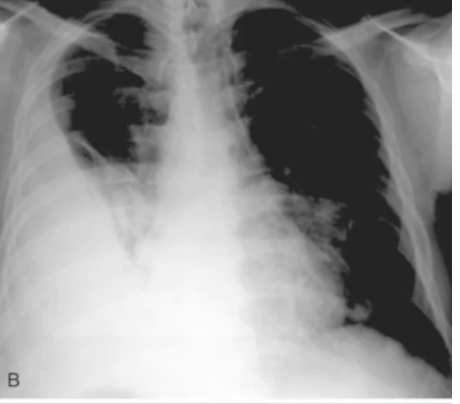

Nocardia - Branching gram positive rod (aerobic)